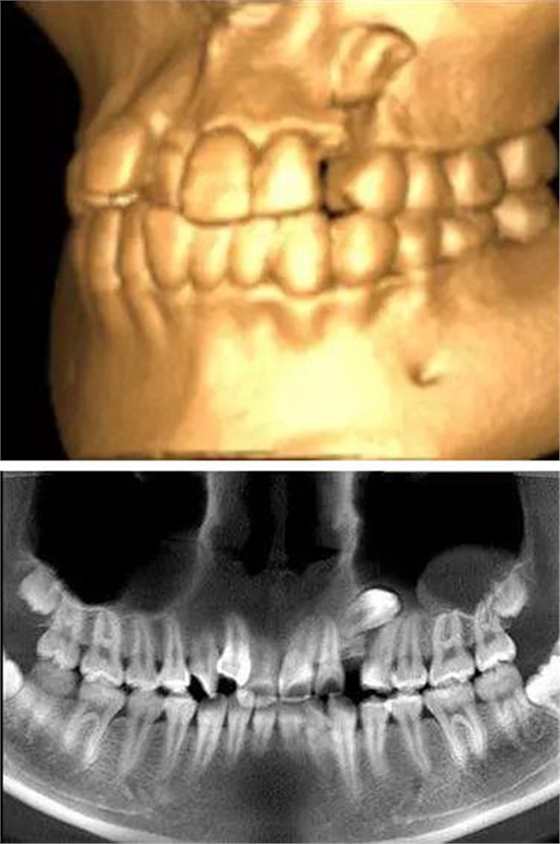

本案:患兒,女,14歲,因牙齒矯正來(lái)院,檢查見(jiàn)83滯留,43未見(jiàn)萌出,拍片發(fā)現(xiàn):43埋伏阻生于31、41、42根尖下方,按照正畸診療計(jì)劃,擬行43拔除術(shù)。

全景片

CBCT顯示